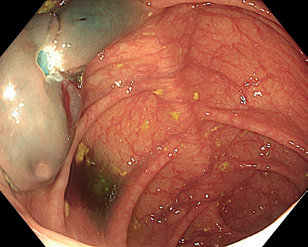

Obr. 3 Stopkatý polyp 0‑Ip zobrazený metodou Narrow Band Imaging.Endoskopická polypektomie (EPE) představuje základní a nejčastěji využívanou terapeutickou proceduru v oblasti gastrointestinální endoskopie. Princip EPE spočívá v naložení polypektomické kličky na stopku stopkatého polypu (0‑Ip), která je tvořena zdravou sliznicí a submukózou, následně je tato stopka přerušena kombinací mechanické síly při uzavření smyčky a elektrického koagulačního proudu (technika známá jako „hot snare“) (obr. 3–5). U rizikových polypů (šíře stopky nad 10 mm či velikost polypu nad 20 mm) se pro minimalizaci rizika krvácení doporučuje před resekcí stopku infiltrovat roztokem adrenalinu, popř. na stopku naložit endoklipy nebo použít odnímatelnou smyčku, známou též jako „endo­loop“, která po resekci polypu zůstává na stopce (obr. 6). EPE se často využívá i pro resekci malých plochých nebo přisedlých lézí (0‑IIa, 0‑Is) s průměrem ≤ 10 mm (obr. 7), a to obvykle pouze v mechanickém režimu bez využití elektrické koagulace (technika známá jako „cold snare“). Tato metoda snižuje riziko pozdějšího krvácení a vzniku koagulačního syndromu. „Resekce“ diminutivních lézí pomocí biop­tic­kých kleští, běžně používaná v minulosti, byla do značné míry opuštěna pro riziko inkompletní resekce a nahrazena právě „cold snare“ polypektomií. Klešťovou resekci je nadále možno použít jen u lézí do velikosti 3 mm. Použití elektrokoagulačních kleští („hot forceps”) se obecně nedoporučuje.